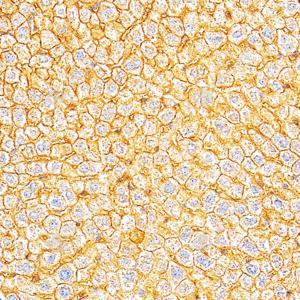

IHC检测Cytokeratin 18蛋白(货号 GB15232). 样品: 人肝癌, 4%多聚甲醛 (货号G1101) 固定12-24小时. 抗原修复: 柠檬酸抗原修复液(干粉, pH 6.0) (G1201), 高压锅均匀喷气计时2分钟. —抗: 1: 500稀释, 4℃ 孵育过夜. 二抗: S-vision免疫组化多聚二抗(山羊抗小鼠), 即用型(货号G1301), 室温孵育20分钟. |